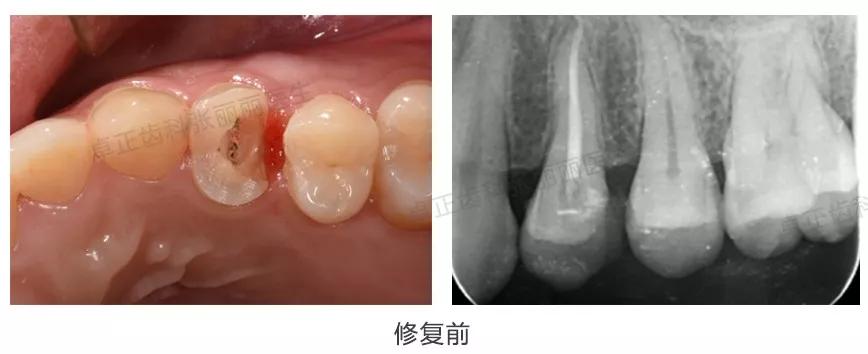

▍ 嵌体

当后牙牙体缺损较大、充填物反复脱落、较大邻面龋坏或缺损,同时患牙又是活髓时,建议嵌体修复。当缺损范围更大,需要覆盖部分或全部牙尖时,称为高嵌体。有关嵌体修复的优点及流程等可参考《牙齿缺了一大块,还能补上吗?》。

临床案例:患者多年前左下6充填治疗,继发龋,去净旧充填体及龋损后,见牙齿缺损较大,选择嵌体修复。